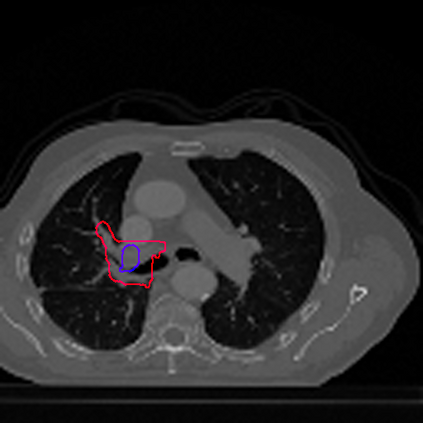

Lung cancer is a leading cause of death in most countries of the world. Since prompt diagnosis of tumors can allow oncologists to discern their nature, type and the mode of treatment, tumor detection and segmentation from CT Scan images is a crucial field of study worldwide. This paper approaches lung tumor segmentation by applying two-dimensional discrete wavelet transform (DWT) on the LOTUS dataset for more meticulous texture analysis whilst integrating information from neighboring CT slices before feeding them to a Deeply Supervised MultiResUNet model. Variations in learning rates, decay and optimization algorithms while training the network have led to different dice co-efficients, the detailed statistics of which have been included in this paper. We also discuss the challenges in this dataset and how we opted to overcome them. In essence, this study aims to maximize the success rate of predicting tumor regions from two dimensional CT Scan slices by experimenting with a number of adequate networks, resulting in a dice co-efficient of 0.8472.